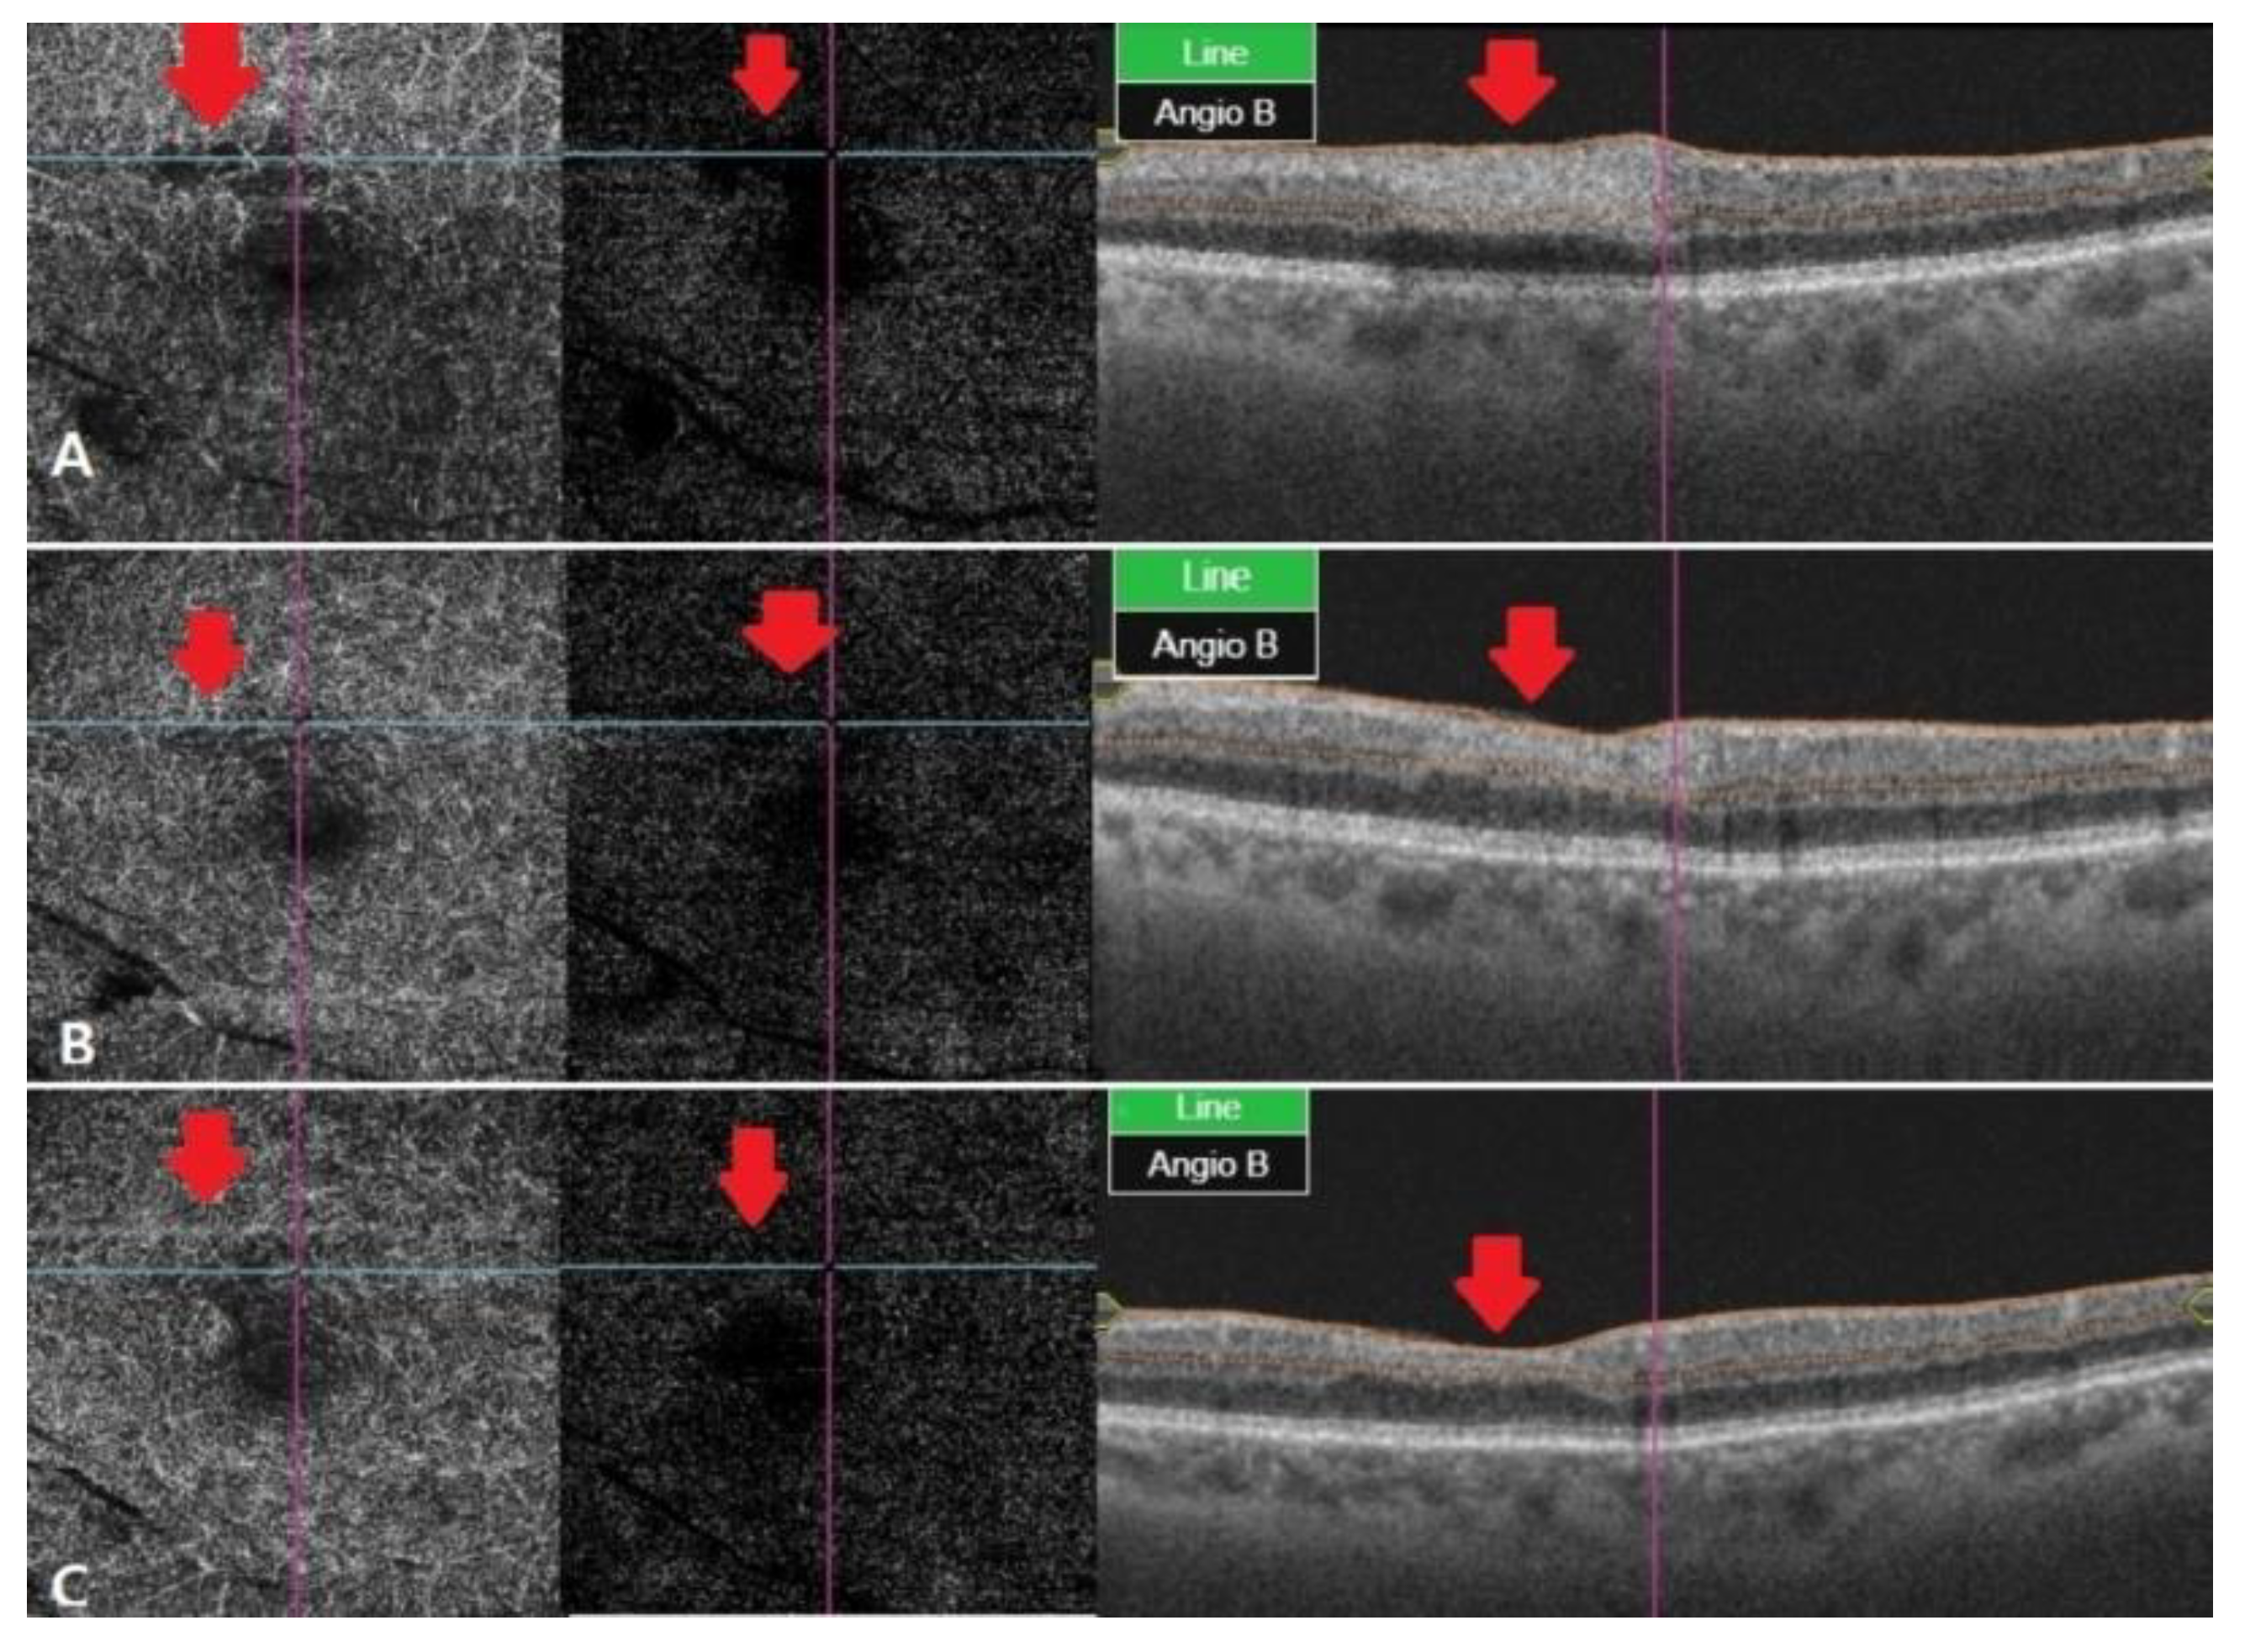

The diagnosis was cilioretinal artery occlusion with branch retinal artery occlusion (BRAO). Two weeks later, the IOP measured in both eyes was 14/13, visual acuity was 20/20 in the right eye, 20/63 in the left eye, with slight difference tobefore. Optical coherence tomography (OCT) showed that the edema remained, but the size of PED slightly decreased.

At a one month follow-up, there was no change in the IOP, but the patient’s vision improved to 20/32 in the left eye, compared with the previous examinations. Fundus examination showed reduced ischemic lesions in the perimacular area, and the overall artery flexus defect showed a slight improvement in OCT angiography, but some ischemic lesions remained. Tests performed using the Humphrey visual field analyzer (30-2 program) showed preserved function in the perimacular area. Two months later, visual acuity was still 20/32 in the left eye, but ischemic lesions in the retina recovered almost completely. The capillary perfusion also improved in OCT angiography, and the patient is currently under outpatient follow-up care (

Figure 2 and

Figure 3).